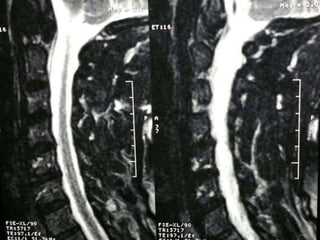

47 year old woman with 6 month h/o neck stiffness and pain with

left UE paresthesias into

The elbow forearm and hand especially IF/thumb

Note:the black line directly posterior to the vertebral bodies and relative

Thinning of spinal cord, note normal disc height

47 year oldwoman with 6 month h/o neck stiffness and pain with left UE paresthesias into The elbow forearm and hand especially IF/thumb

Note:the black linedirectly posterior to the vertebral bodies and relative Thinning of spinal cord, note normal disc height